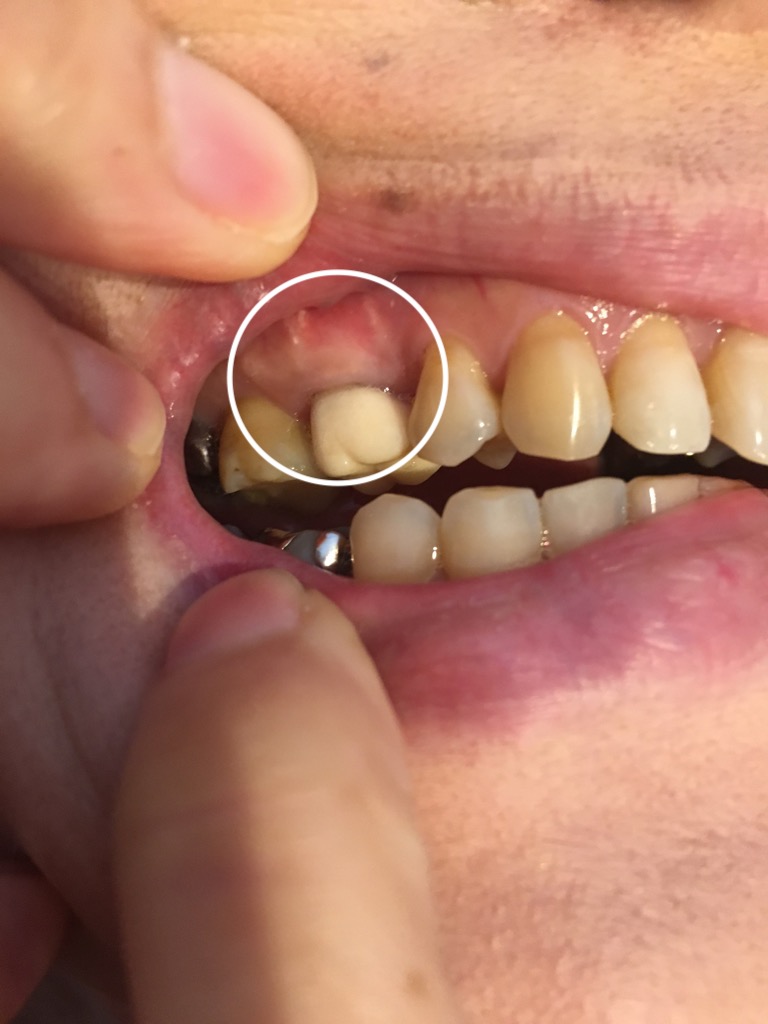

こちらは治療前の画像です。

こちらは、そのときの画像です。

外科手術のために仮歯を入れてあります。歯茎の腫れは無くなりました。